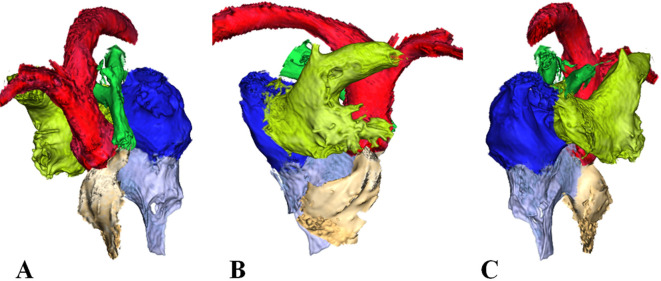

The necropsy of a 2-day-old Noma horse that died of weakness showed an enlarged cardiac base and a narrow cardiac apex, suggesting cardiac malformation. The excised heart underwent imaging to investigate its luminal structure. On three-dimensional magnetic resonance imaging, the right atrium and right ventricle were discontinuous. The right atrium communicated with the left atrium and the left ventricle communicated with the right ventricle. The lumen narrowed near the pulmonary artery valve. Since the same findings were observed on gross examination, the foal was diagnosed with tricuspid atresia with ventricular and atrial septal defects, along with subvalvular pulmonic stenosis.